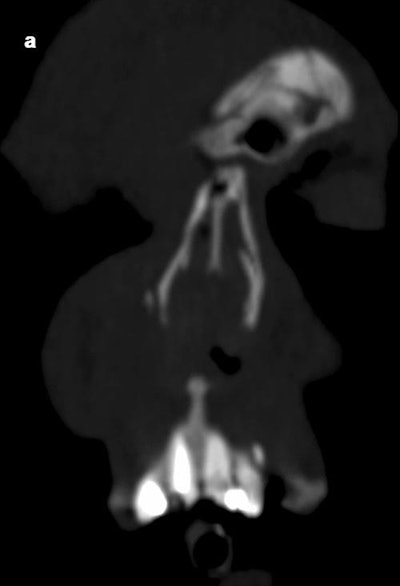

A radiologist with seven years of experience reanalyzed the scans for possible dental trauma findings. The images were evaluated using 3D reconstructions, and the radiologist and a consultant radiologist with 17 years of experience reached a consensus on any cases that were unclear.

The most common findings were dislodged teeth and fractured crowns, which occurred in 49 and 46 patients, respectively. Other findings included root fractures, extrusions, and intrusions.